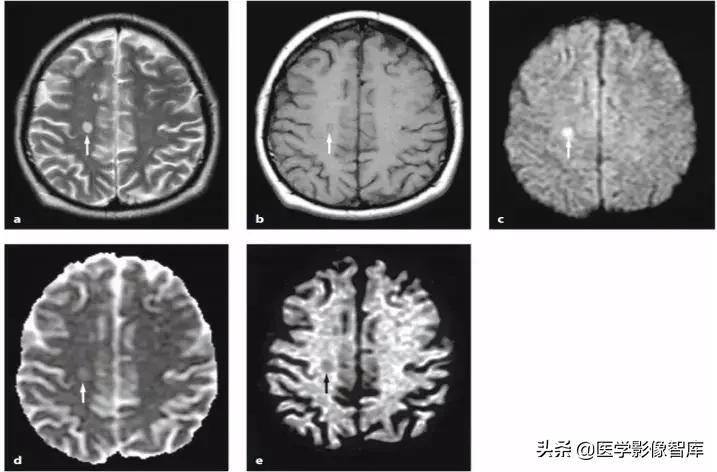

对于有明确癫痫发作病史的患者,癫痫介导的脑部影像学改变需要考虑,不同于癫痫的病因(肿瘤、FCD 等),癫痫介导的脑部影像学改变往往是可逆的,磁共振上大多表现为 T2WI 高信号,约半数表现为 DWI 高信号,常见的受累部位包括皮层 / 皮层下、基底节区、白质、胼胝体、小脑,而临床上无其他特异性的表现,如图 2 所示。

图 2 42 岁女性,延长的亚临床癫痫持续状态患者所做的两次头颅 MR 结果。A 为 T2WI,B、C、F 为 DWI,D 为 ADC 图,E、G 为 FLAIR,可见发病 4 天时双侧顶枕叶可见明显 DWI 高信号病灶,T2 相也为高信号,ADC 低信号,发病 25 天时,病灶消失